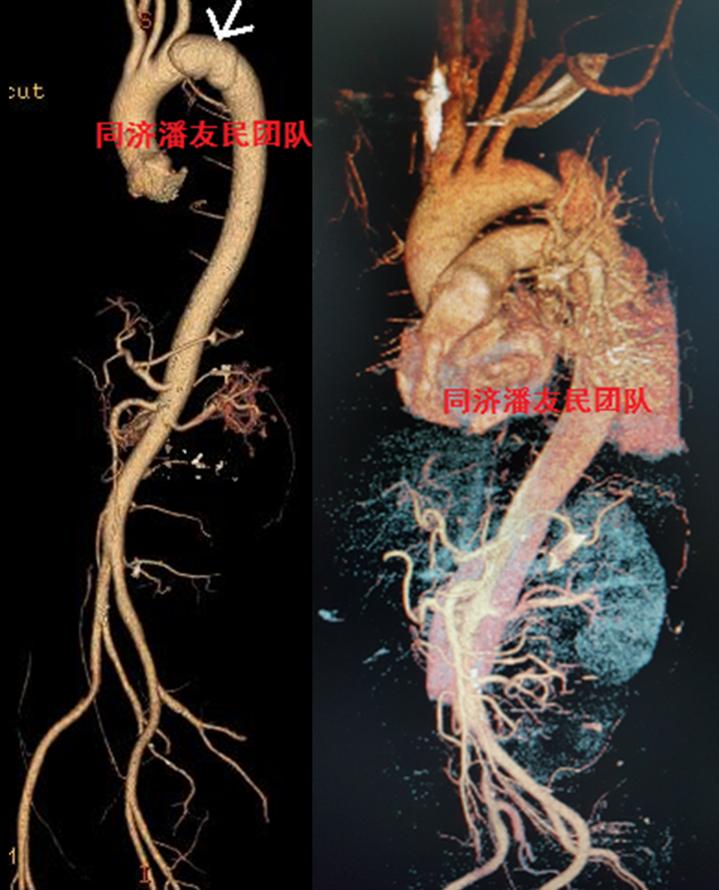

外伤性主动脉夹层进行腔内治疗,腹部外伤情况也进行了相应处理。患者出院前复查CTA,情况良好(图5)。

入院后,胸腹主动脉CTA将主动脉及胸腹腔脏器一起进行全面评估。与图1平扫CT层面对应,图2显示降主动脉夹层。

除了局限性主动脉夹层外,也可以表现为非局限性夹层,即普通类型的降主动脉夹层(图6)。